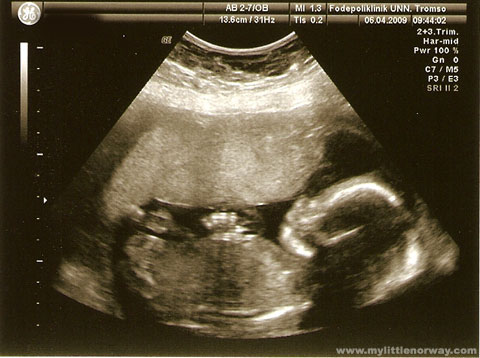

It looks like pre-natal tests for autism may be on the horizon. These scare the hell out of me, for many reasons, but principally because the implications of potentially losing people on the autistic spectrum means a great loss to society.

Pre-natal tests could prove helpful for parents of the autistic community, where they are used to detect autistic traits early, and in turn could lead to better early intervention measures.

Pre-natal testing could be amazing and helpful, for the reasons Baron-Cohen posits above. It could be awful, were it to be used to give parents the option, as they have with Down’s Syndrome, to terminate a pregnancy.

92% of pregnancies in England and Wales that receive a diagnosis of Down’s Syndrome are aborted (figures from 1998). This proportion has not changed since 1989, when Pre-natal testing was introduced. However, there is evidence that changing parental attitudes mean more babies with Down’s Syndrome are being born.